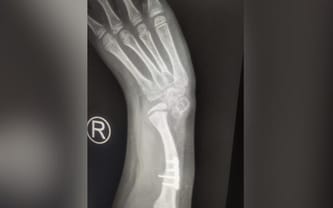

Brak kości przedramienia prawej ręki, brak kciuka prawej ręki, wada słuchu, choroba nerki